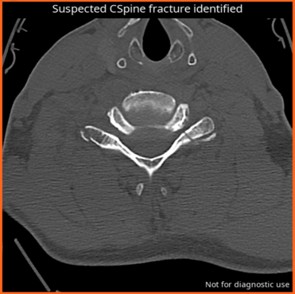

CINA Cspine (FDA)

CINA-CSpine is an AI triage tool that detects acute cervical spine fractures, including those with non-displaced fracture lines and/or displaced fracture fragments on non-enhanced neck CT scans.